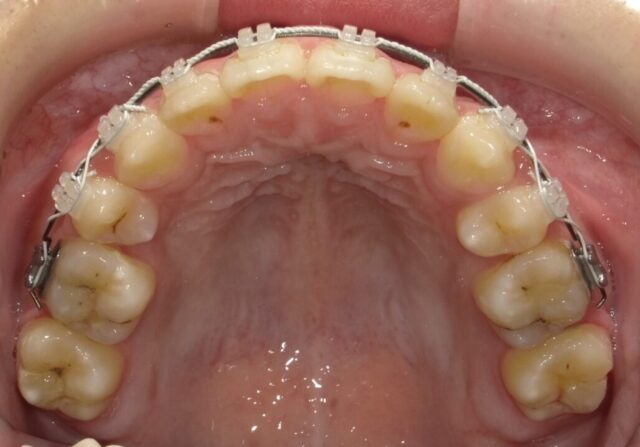

≪上顎咬合面観≫

2025年1月